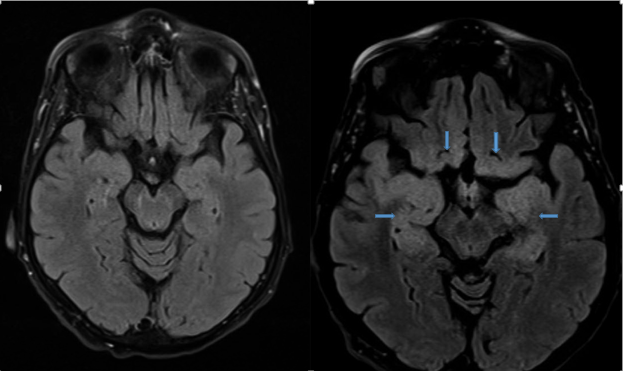

An infectious diseases specialist was consulted, and the patient was treated with intravenous acyclovir and antibiotics for pneumonia. A brain MRI was repeated on the seventh day of hospital admission, the results of which showed extensive cortical edema consistent with a diagnosis of herpes simplex encephalitis (HSE) (Figures).

Figures. T2-weighted fluid-attenuated inversion recovery MRI sequences on day 1 (top left and bottom left) and day 7 (top right and bottom right), the latter of which showed an extensive pattern of abnormal cortical edema suggesting underlying encephalitis in the inferior mesial frontal lobe, insular cortex, and mesial temporal lobe bilaterally (blue arrows).